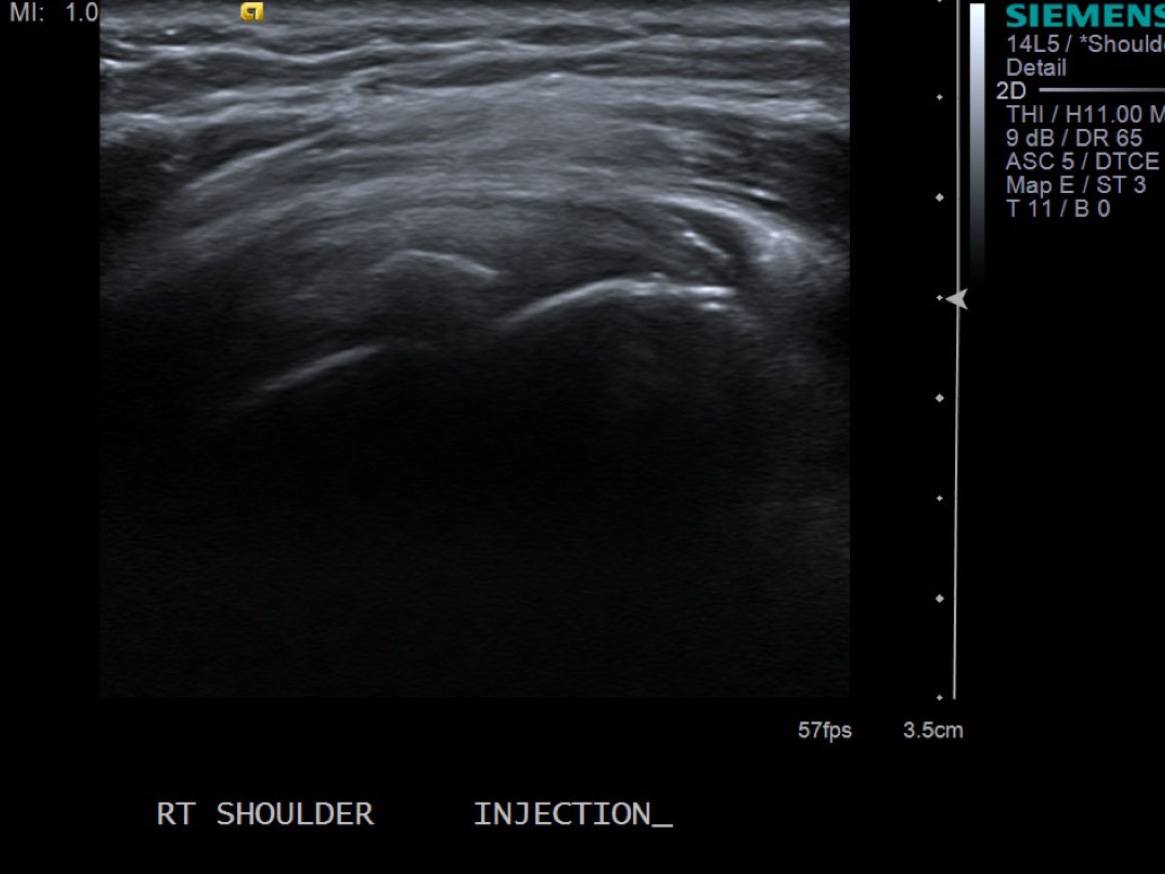

• descriptiondescription

Post procedure scan demonstrating decreased size and decreased central echogenicity of calcific deposit and injectate surrounding it.

14.While keeping 18g needle in place, remove 10cc syringe and redirect needle to the subacromial/subdeltoid bursa. These patients often have subacromial/subdelotid bursitis.